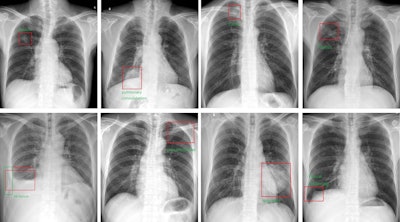

The AI system output the bounding boxes and labels of the lesions to assist radiologists. Image courtesy of the Journal of Imaging Informatics in Medicine.